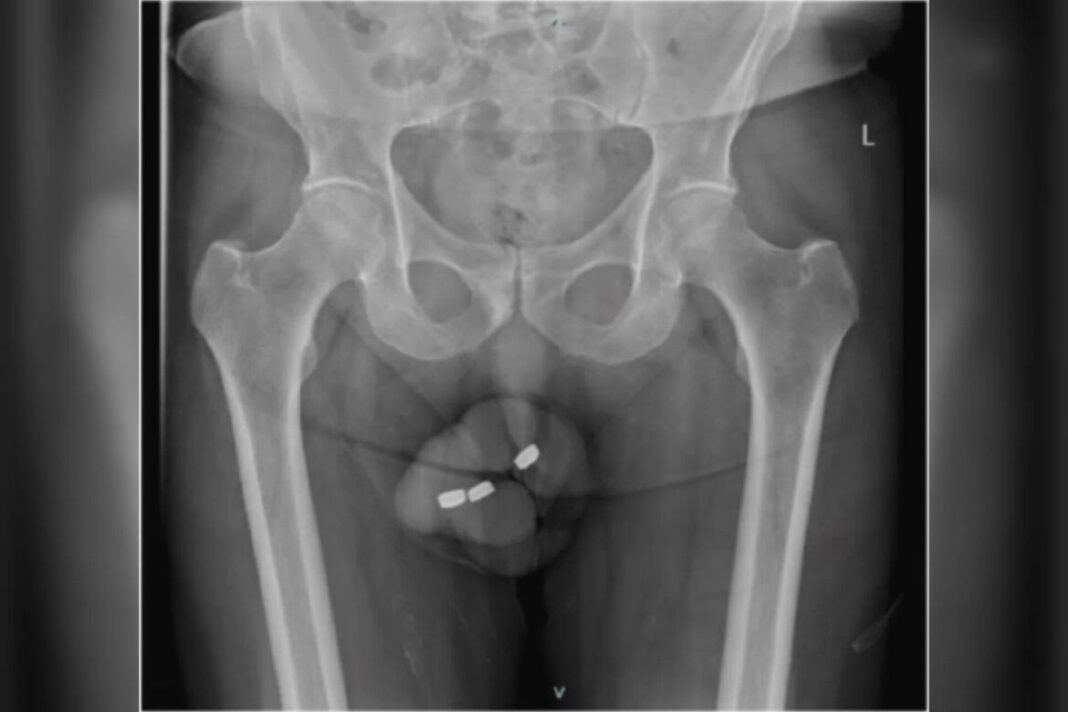

Um idoso procurou uma emergência médica na Austrália com fortes dores no pênis. O paciente, que não foi identificado por razões de privacidade, tinha enfiado três baterias semelhantes às balas tictac na uretra, canal do pênis por onde passa a urina.

Ao chegar ao hospital, o paciente não conseguia urinar e estava com o órgão todo inchado. Além disso, a bateria enfiada por último havia se danificado lá dentro e os médicos temiam o vazamento de elementos corrosivos no corpo do paciente.

Os médicos que atenderam o paciente relataram ter tentado retirar as baterias com pinças, mas a dor impediu que o procedimento atingisse seu objetivo. O recurso seguinte foi sedar o idoso e retirar as baterias em uma operação cirúrgica.

Durante a cirurgia, os médicos descobriram que a uretra do paciente estava queimada por conta do vazamento das substâncias corrosivas. Eles cuidaram das queimaduras, prescreveram antibióticos e deram alta para o homem após três dias.

Os médicos drenaram todo o líquido do pênis em uma nova cirurgia e descobriram que 8 cm da uretra havia necrosado, o que obrigou-os a retirar parte do órgão do paciente, com a substituição do canal por um catéter. O tecido ao redor foi raspado para evitar novas infecções.